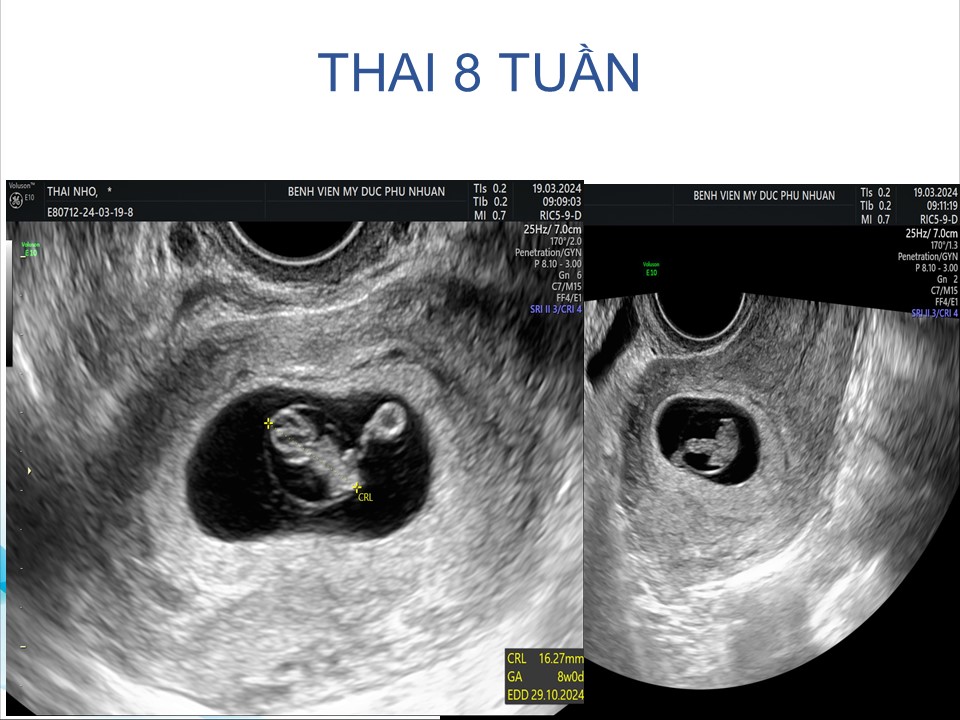

Siêu âm đánh giá khả năng sống của thai giai đoạn sớm

BS. CKI Phạm Thị Phương Anh - BV Mỹ Đức